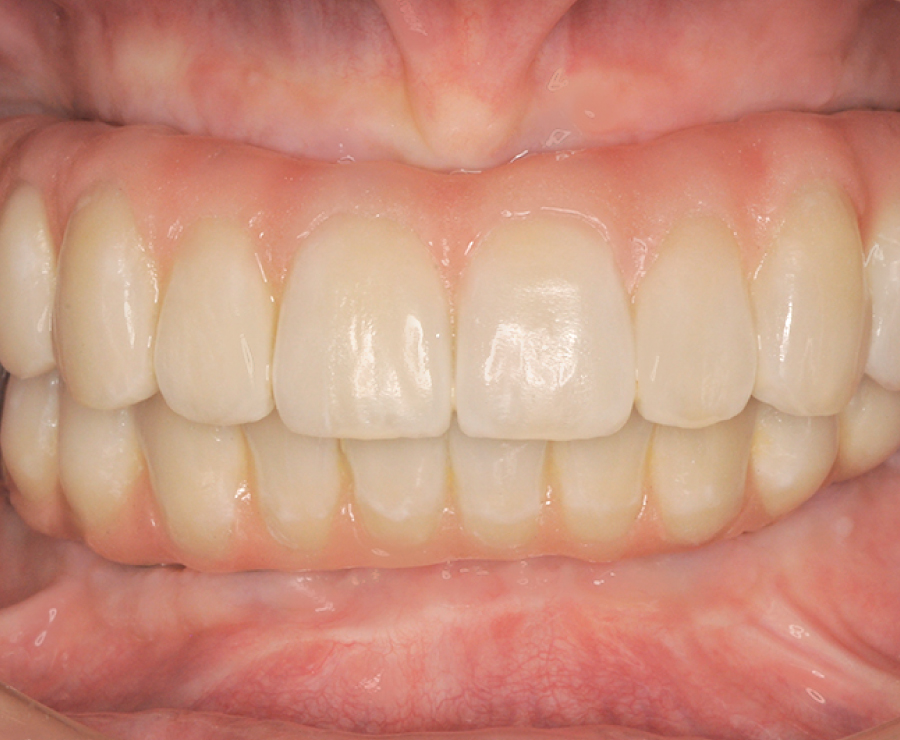

短期間で劇的に見た目改善できる

しっかり何でも噛めるようになる

とびきり美しい上部構造

ただ治すのではなく、美しく治す。しかも、とびっきり美しく治すことにこだわっています。そのため、数々の賞を受賞する腕の良い歯科技工士と連携して歯をデザインしています。